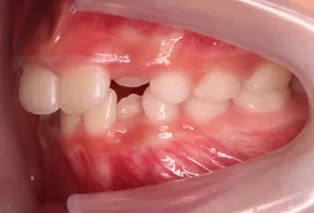

Photos intra-orales